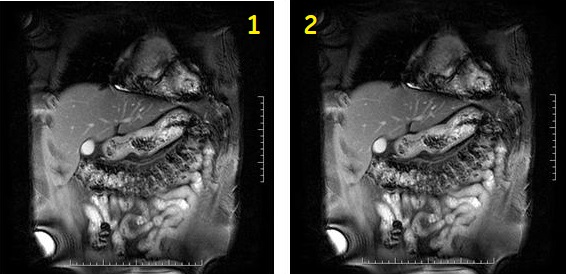

Figure 2. 2D Fat SAT Fiesta with MPH in sequential mode

Table 1. Image legend Number Description 1 First phase 2 Second phase Figure 3. 2D Fat SAT Fiesta with 2 slices and MPH in interleave mode. 1 = 1st phase, 2 = 2nd phase